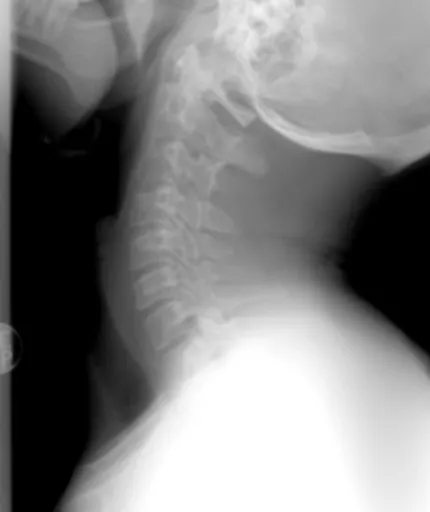

허리 협착증 치료의 가장 첫 번째 단계는 바로 정확한 진단 이에요. 단순히 허리가 아프다고 해서 다 같은 원인이 아니기 때문이죠. 의사 선생님께서 직접 여러분의 증상을 자세히 듣고(문진), 다리의 힘이나 감각을 확인하는 신경학적 검사를 하실 거예요. 그리고 엑스레이, MRI, CT 같은 영상 검사를 통해 척추관이 얼마나 좁아졌는지, 어떤 신경이 눌리고 있는지 등을 꼼꼼히 살펴보게 됩니다. 이 과정을 통해 여러분에게 딱 맞는 허리 협착증 치료 계획을 세울 수 있는 거랍니다.